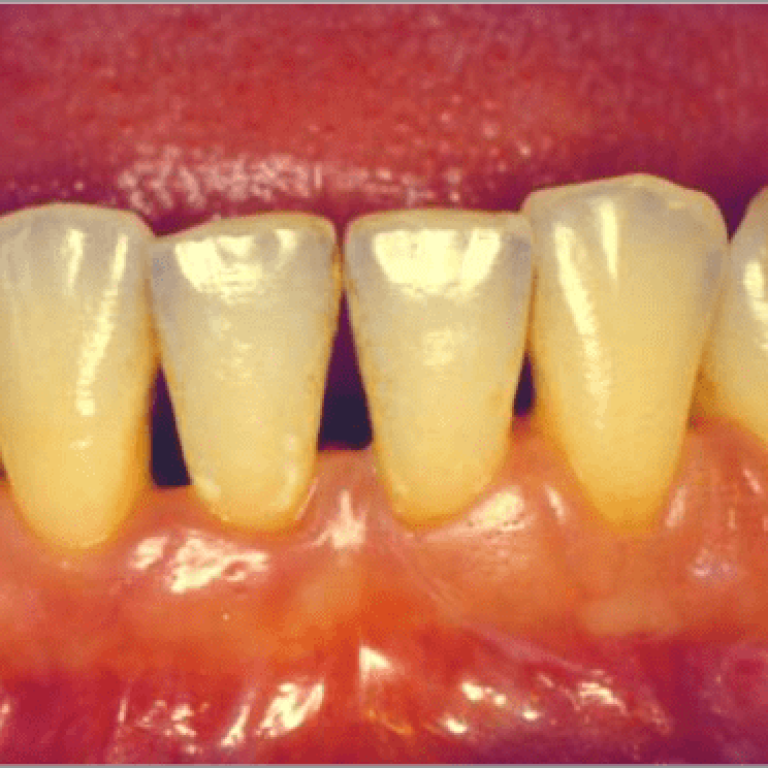

Nel costruire un programma igienico efficace e di qualità vanno considerate 4 importanti variabili: il tempo impiegato, la …